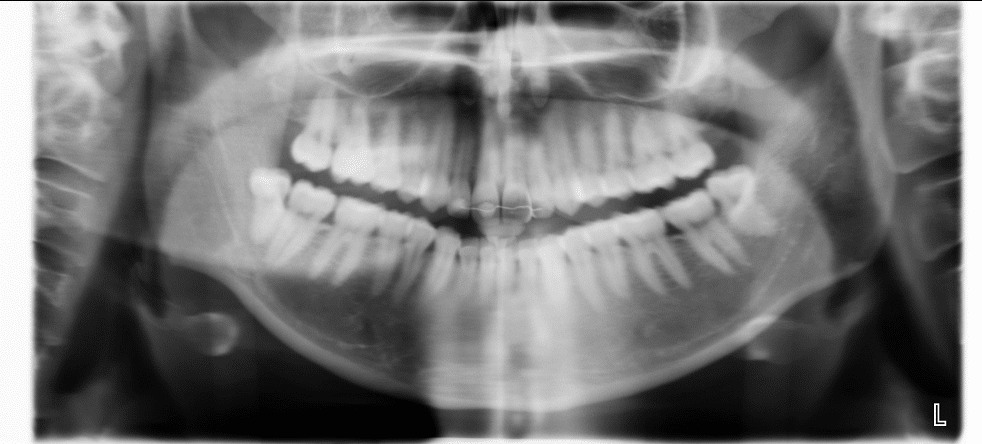

Er røntgenstråling noget vi skal være nervøse for? Det er et spørgsmål vi tit får, og som der kan svares både ja og nej til. I gamle dage, og her mener vi for bare få år tilbage i tiden, afgav røntgenapparaterne væsentlig større strålingsdosis end de gør i dag. Det er udviklingen der har gjort at det nye og moderne udstyr kun afgiver en meget lille strålingsdosis, og samtidigt faktisk tager bedre billeder.

For at sætte det i perspektiv, så giver en tur i en Orthopan scanner, en dosis der svarer til et døgns normal baggrundsstråling, eller hvad du ville få i et charterfly på under en time. Det er blot en af fordelene ved udstyr der er nyt og topmoderne.

Panorama røntgen